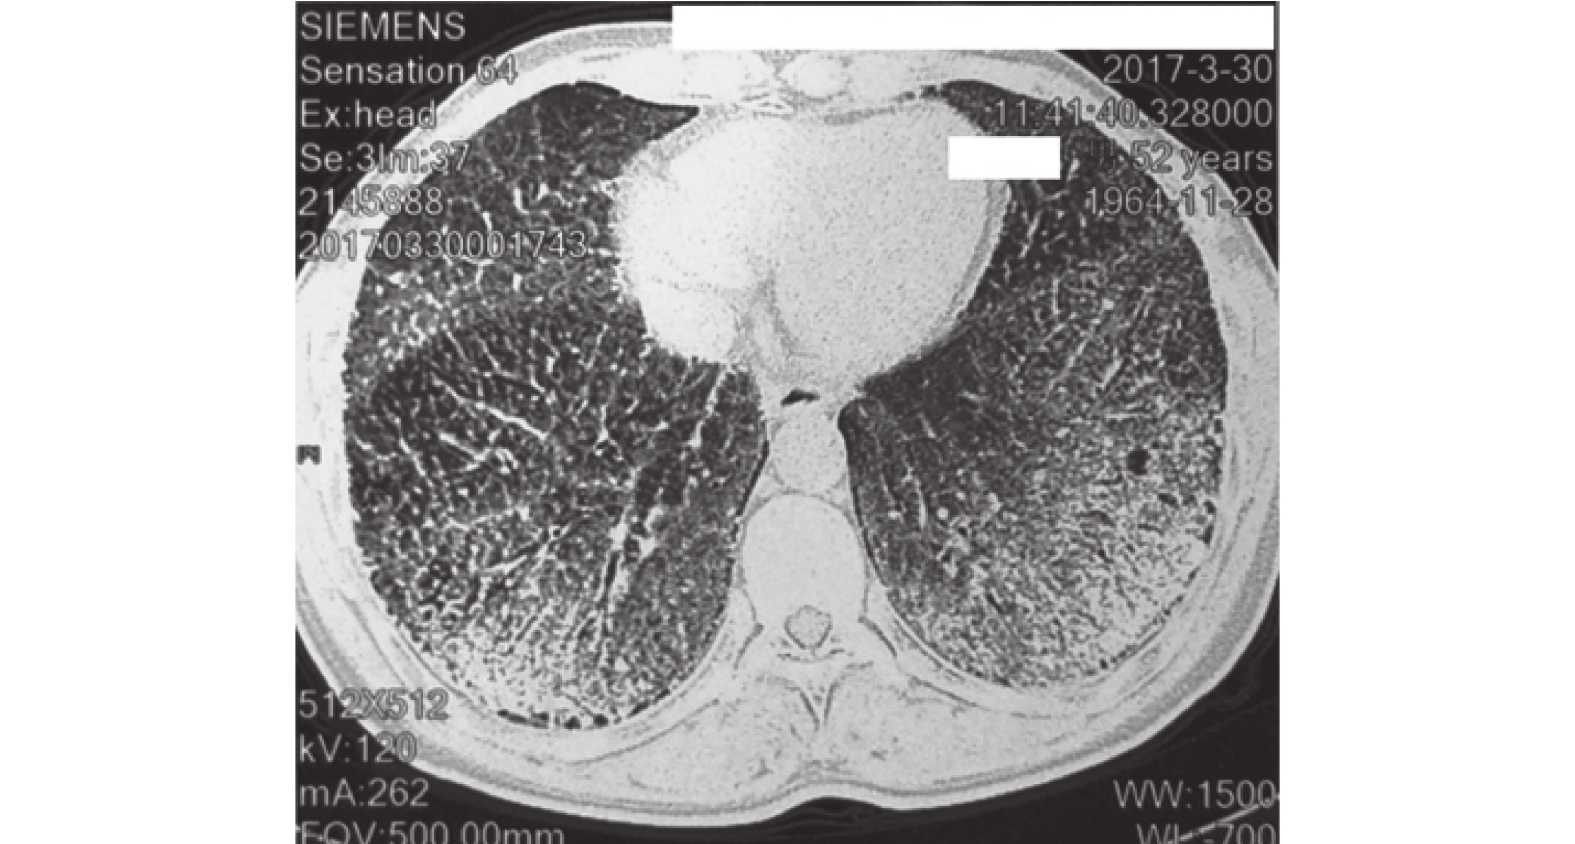

患者男性,51 歲,因“反復間斷咳嗽 30 年,再發伴胸悶氣喘 3 周”于 2017 年 10 月來我院就診。入院前當地醫院胸部 X 及 CT 檢查顯示兩肺實質遍布彌漫性砂礫狀高密度影,雙側氣胸,左側為著,壓縮約 20%。既往有 30 年吸煙史,每日約 20 支。體檢:神志清楚,口唇輕度紫紺,兩肺呼吸音減低,兩下肺聞及 velcro 啰音,手指杵狀指。血氣分析(吸空氣):pH 7.36,氧分壓 82 mm Hg(1 mm Hg=0.133 kPa),二氧化碳分壓 40.9 mm Hg,氧飽和度 95.5%。血常規:白細胞 8.7×109/L,中性粒細胞百分比 59.5%,淋巴細胞百分比 27.0%,嗜酸性粒細胞百分比 7.4%,紅細胞計數 4.96×1012/L,血紅蛋白濃度 148 g/L,血小板計數 455×109/L,C 反應蛋白 7.70 mg/L,血沉 70 mm/1 h。生化正常,血鈣、鎂、磷正常。凝血功能及 D 二聚體正常。腫瘤指標:糖類抗原 15-3 69.40 U/ml,糖類抗原 125 115.18 U/ml,其余包括癌胚抗原、細胞角蛋白 19 片段、鱗狀細胞癌抗原、神經元特異烯醇化酶正常。免疫球蛋白電泳正常。自身抗體系列:抗核抗體 1∶100 陽性。心電圖:竇性心律,不完全性右束支傳導阻滯。腹部超聲及心臟彩超未見異常。肺功能報告:用力肺活量占預計值百分比 51.7%,第 1 秒用力呼氣容積(forced expiratory volume in one second,FEV1)占預計值百分比 53%,一口氣呼吸法肺一氧化碳彌散量(diffusing capacity of the lung for carbon monoxide,DLCO)6.13 ml/(mm Hg·min),占預計值百分比 27.7%,DLCO 與肺泡通氣量的比值 38.5%,提示中度限制性通氣功能障礙,重度彌散功能障礙。胸部高分辨率 CT:兩肺野見彌漫分布砂礫狀高密度影,密度兩下肺為甚,彌漫成片,肺間質廣泛增厚,兩中上肺野可見肺大皰,兩側胸膜局部增厚,考慮 PAM(圖 1a、b)。為進一步明確診斷,入院后行支氣管鏡檢查和支氣管肺泡灌洗液檢查均無明顯的異常發現。遂行 CT 引導下經皮左肺下葉肺穿刺,活檢病理報告:破碎支氣管及肺泡組織,其間見散在鈣化灶,傾向 PAM,特染:過碘酸希夫(+/–),甲基紫(+/–),剛果紅(–)。病理切片顯示肺泡上皮可見大量鈣鹽沉積(圖 1c)。

a. CT 檢查像,雙上肺野彌漫分布鈣化影,右側更甚,肺間質廣泛增厚,可見肺大皰,兩側胸膜局部增厚;b. CT 檢查像,雙下肺野見彌漫成片分布砂礫狀高密度影,兩側胸膜局部增厚,可見“黑胸膜線”;c. 病理檢查像,蘇木精-伊紅×100,肺泡上皮可見大量鈣鹽沉積

胸部 X 線檢查是發現本病最基本的手段,表現為兩肺彌漫性分布、邊緣銳利、均勻大小、呈鈣化密度的砂礫樣微結節,中下肺野更易累及[9]。隨著病情進展,兩肺結節影密集,可出現病灶聚集融合,心膈模糊,呈“沙塵暴”樣改變。疾病進展期可見白肺征[10]。胸部高分辨率 CT 中常見的特征是雙肺磨玻璃影,彌漫分布的微小結節,小葉間隔增厚,小葉中心性肺氣腫,胸膜間質增厚,胸膜鈣化和周圍支氣管擴張[11]。肺尖大皰伴有氣胸是另一典型特征。部分呈肺間質纖維化的表現。胸膜下有薄壁小氣囊形成的“黑胸膜線”。縱隔窗顯示肺野內不規則點狀、條狀致密影,胸膜下可融合成片。本例患者的胸部高分辨率 CT 顯示兩肺野見彌漫分布的砂礫狀高密度影,密度兩下肺為甚,彌漫成片,肺間質廣泛增厚,兩中上肺野可見肺大皰,兩側胸膜局部增厚,由于其典型表現,從影像學上就初診為 PAM。